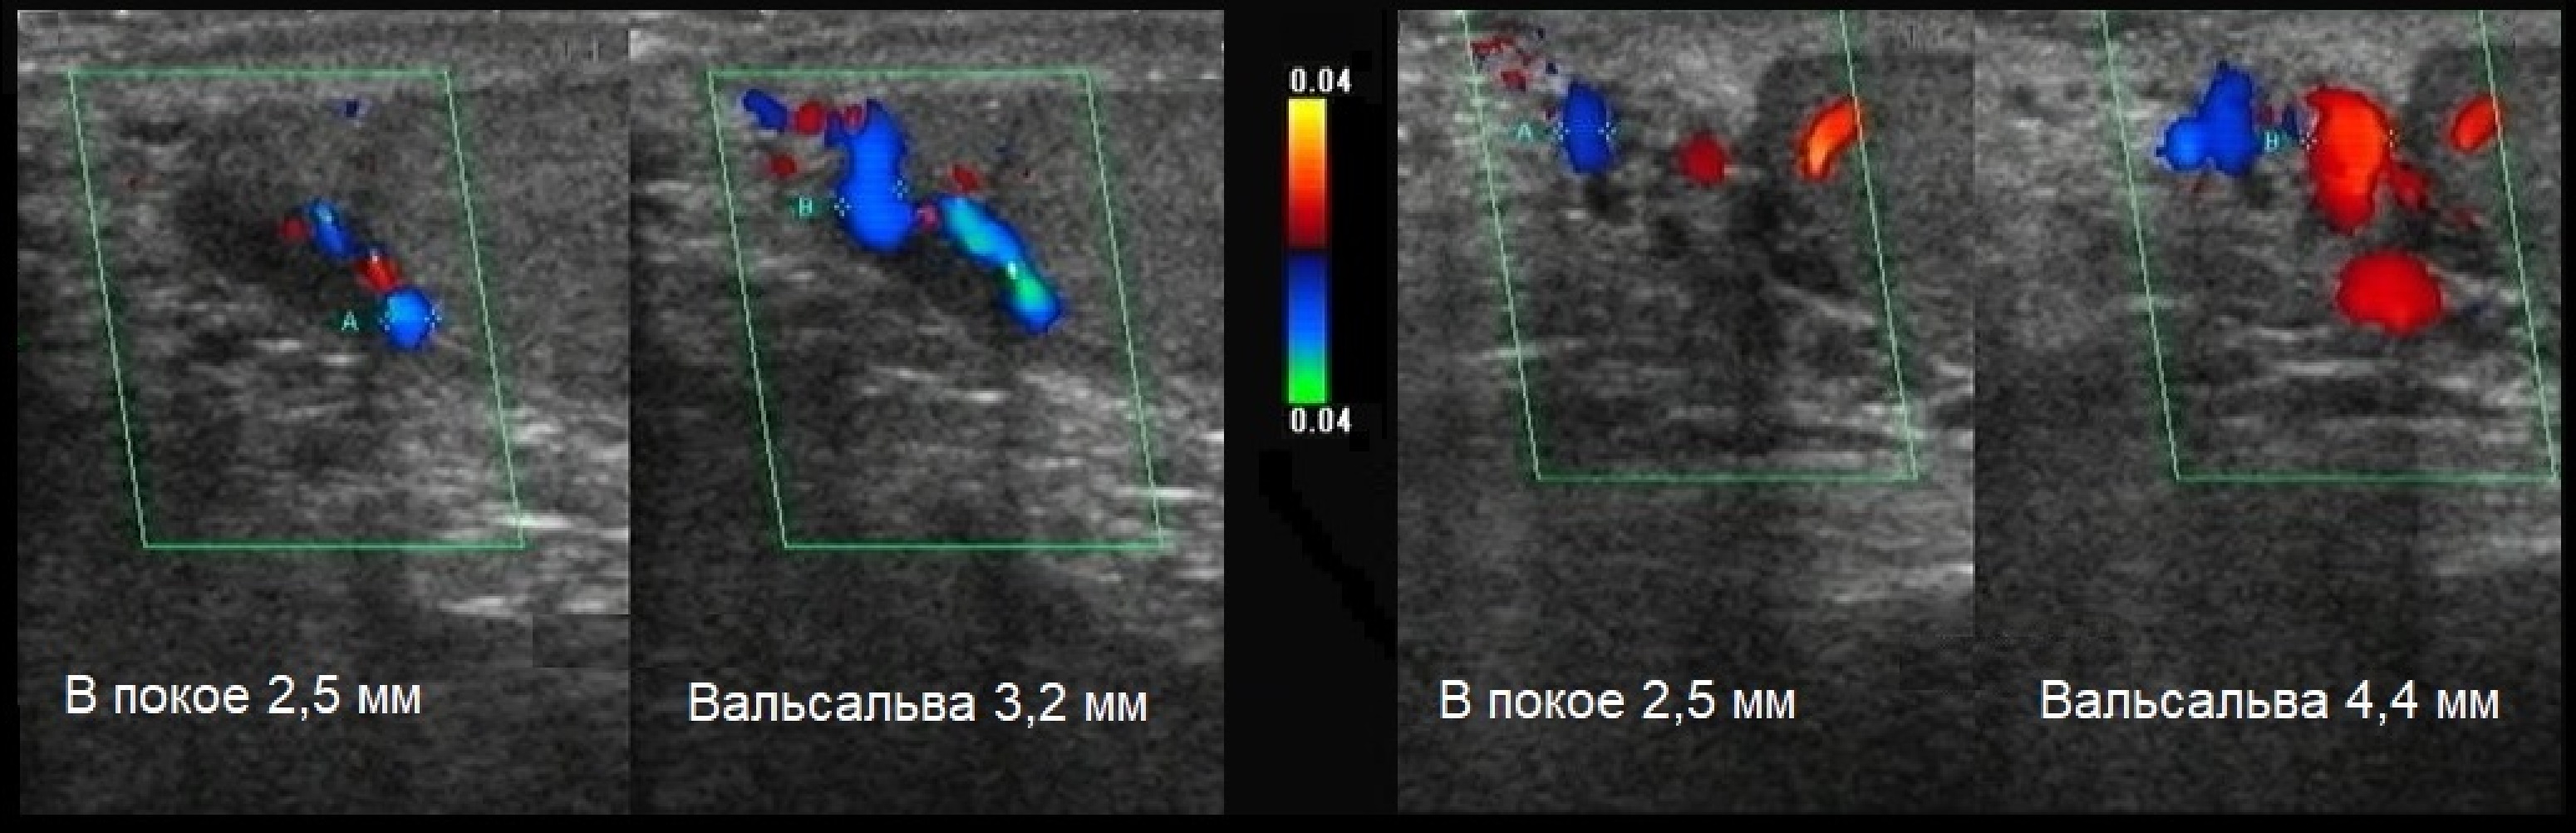

Особенности и диагностика левостороннего кровотока